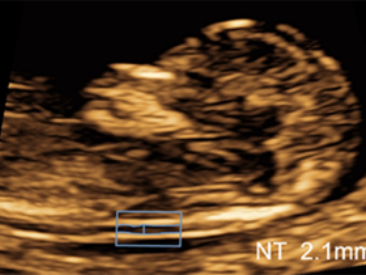

Images cliniques